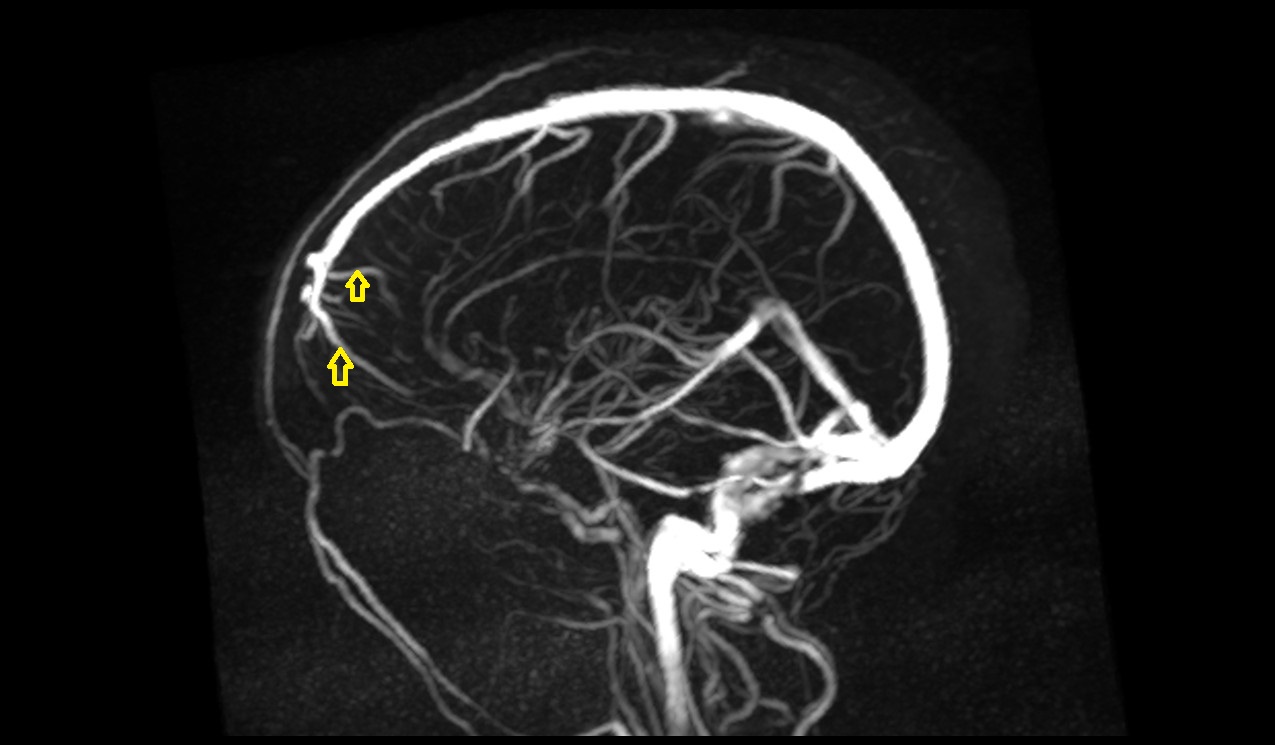

- Anterior cerebral artery

- Middle cerebral artery

- Superior anastomotic vein

- Inferior anastomotic vein (Vein of Labbé)